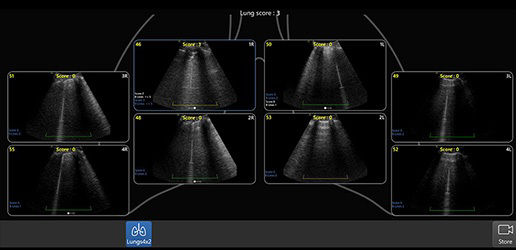

Review lung segment images in one view with Lung Diagram

A single view diagram of anatomical lung segments with one click image storing. Keeps track of segmental lung assessment and can be helpful in showing trends in response to therapy.